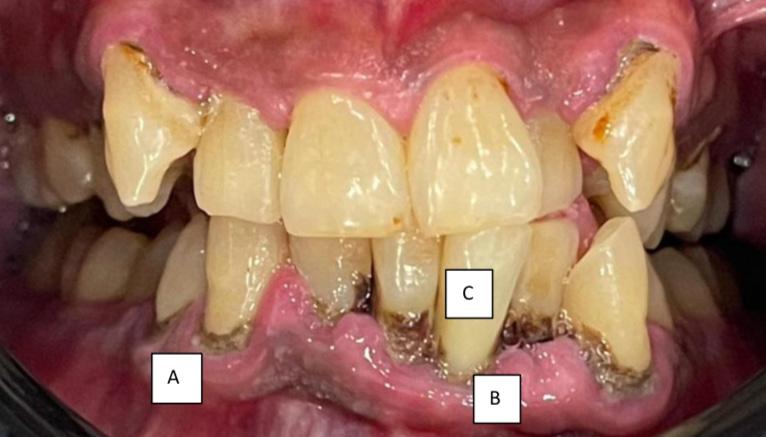

Sebelum rawatan penskaleran Selepas rawatan penskaleran Keadaan gigi yang tidak pernah melakukan rawatan penskaleran. (A) menunjukkan tartar yang berkumpul pada gusi (B) gusi berwarna merah, bengkak dan lembut seperti span (C) gigi kelihatan lebih panjang dan bergoyang akibat penurunan gusi dan tulangLUMUT, 10 Oktober 2023 - Sambutan Hari